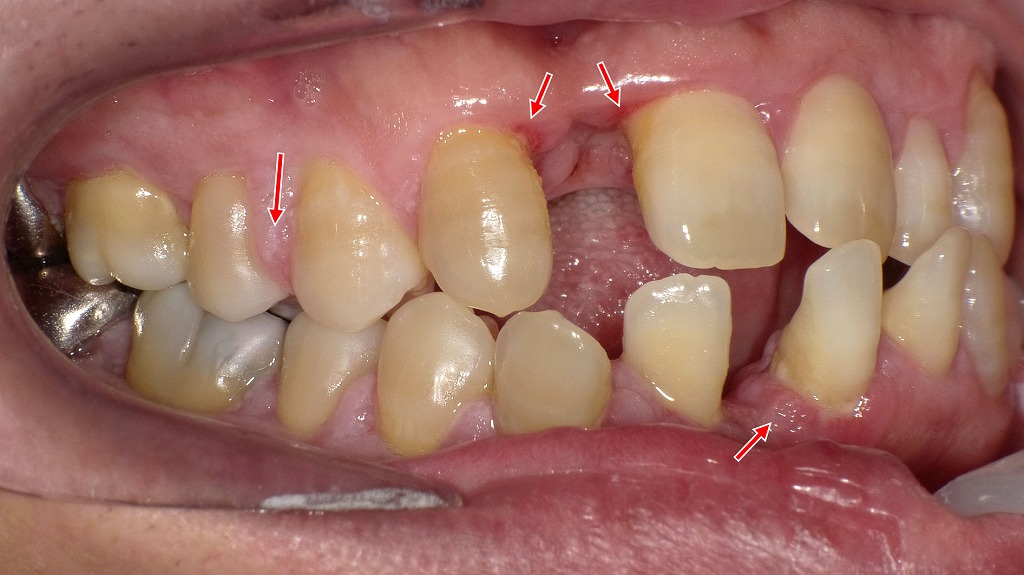

赤矢印で示す部分では、歯を支える歯槽骨が大きく吸収され、歯ぐきが下がり歯の根が露出しています。これは重度歯周病にみられる典型的な所見で、炎症が長期間続いた結果、歯周組織が破壊された状態です。ここまで進行すると歯の動揺が強くなり、最終的には抜歯が必要となる場合もあります。早期発見・早期治療が歯を守るために重要です。